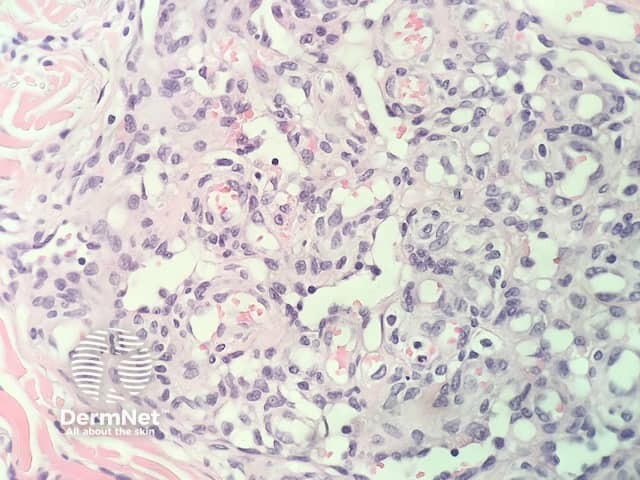

In glomeruloid haemangioma, the histopathology shows numerous dermal ectatic vascular spaces lined by flat endothelial cells. Inside these dilated vascular spaces are a conglomeration of capillaries lined by plump, swollen endothelial cells, filled with red blood cells, resembling renal glomeruli (figures 1–4).